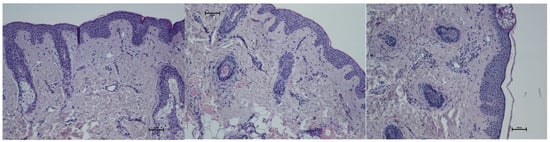

- Histological assessment

- 0: loose, regular fibers;

- 1: loose, irregular fibers;

- 2: dense fibers;

- 3: compact, coarse fibers.

- Results of histological assessment